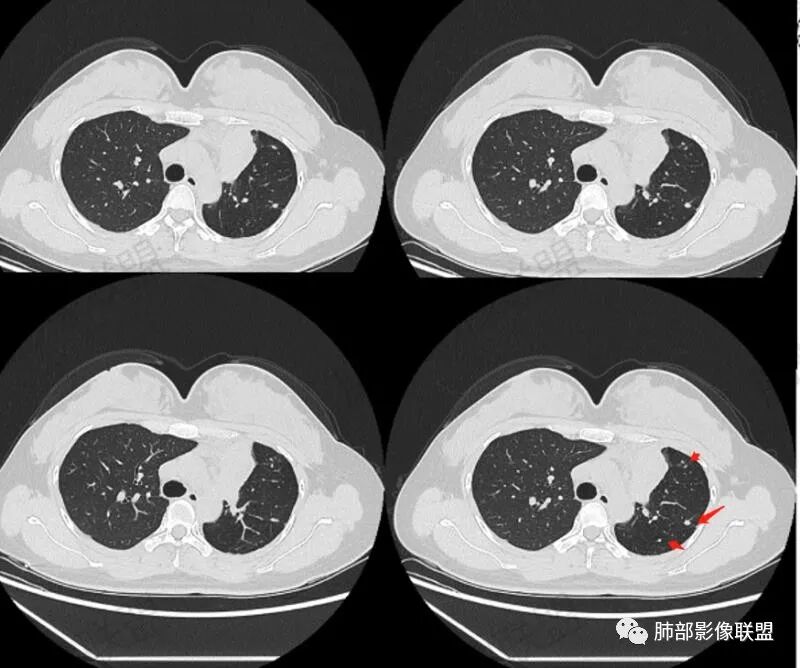

年轻女性,咳嗽咳痰一个月,左肺体积缩小,左肺尖部胸膜下实变影,宽基底与胸膜相贴,病灶边缘平直收缩,部分略膨隆,病灶下方可见支气管挤压,肺窗所示:周围伴有多发结节部分可见树丫征,纵隔窗可见病灶与纵隔胸膜黏连,部分与左肺动脉分界欠清,平扫密度尚均匀,增强扫描不均匀强化,内部可见多个低密度坏死,伴有条状血管影,纵隔淋巴结略有肿大。

女性,29岁,咳嗽咳痰,痰中带血1月余,CT示左肺尖胸膜下纵隔旁不规则实变影,内部可见小点状钙化灶,支气管略狭窄,增强可见低密度不强化区,粘液栓?实性成分明显不均匀强化,局部与左肺动脉分界不清,另左肺可见多发小结节,考虑为恶性,黏表可能,鉴别结核

胸部CT:左肺体积缩小,左肺上叶前段纵隔旁胸膜下大片实变影,边缘清楚、匀齐、平直收缩,部分略膨隆,周围多发结节、树芽卫星灶,纵隔窗病灶与纵隔胸膜黏连,实变内多发点状钙化。平扫密度尚均匀,增强扫描不均匀明显强化,多个低密度区,呈仙人掌样,伴有条状血管影,考虑慢性炎症伴左上叶前段支气管闭塞,TB?鉴别黏表、腺癌等。

周围多发小斑片,病灶内可见点状钙化,29岁女性,警惕结核;